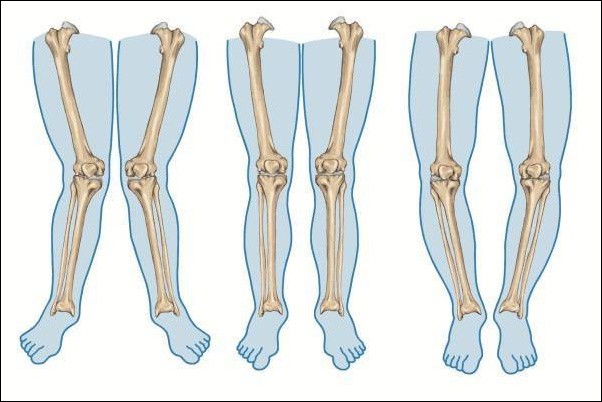

Ngoài vai trò trong đông máu, vitamin K còn có tác dụng tích cực đối với sức khỏe xương. Nó giúp điều chỉnh sự chuyển hóa canxi trong cơ thể, từ đó ảnh hưởng đến mật độ xương. Các nghiên cứu đã chỉ ra rằng vitamin K có thể làm giảm nguy cơ gãy xương ở người lớn tuổi bằng cách cải thiện cấu trúc xương và tăng cường khả năng hấp thụ canxi.

Khi cơ thể thiếu vitamin K, canxi có thể tích tụ trong các mô mềm thay vì được lưu trữ trong xương, gây ra tình trạng loãng xương và tăng nguy cơ gãy xương. Do đó, việc bổ sung vitamin K đầy đủ là rất cần thiết để duy trì sức khỏe xương.

Thiếu vitamin K cũng có thể ảnh hưởng đến sức khỏe xương. Người thiếu vitamin K có nguy cơ cao mắc các bệnh lý liên quan đến xương như loãng xương và gãy xương. Các nghiên cứu đã chỉ ra rằng vitamin K có vai trò quan trọng trong việc duy trì mật độ xương và cấu trúc xương.

Nếu bạn cảm thấy đau nhức xương khớp hoặc có tiền sử gãy xương, hãy xem xét lại chế độ ăn uống của mình để đảm bảo rằng bạn đang nhận đủ vitamin K.